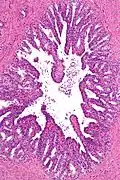

Histology of seminal vesicle glands on H&E stain. They may mimic prostatic adenocarcinoma by crowded glands with enlarged hyperchromatic and irregular nuclei, but will have inconspicuous nucleoli and coarse refractile golden brown lipofuscin granules.[7]

The inner lining of the seminal vesicles (the epithelium) is made of a lining of interspersed column-shaped and cube-shaped cells.[8] There are varying descriptions of the lining as being pseudostratified and consisting of column-shaped cells only.[9] When viewed under a microscope, the cells are seen to have large bubbles in their interior. This is because their interior, called cytoplasm, contains lipid droplets involved in secretion during ejaculation.[8] The tissue of the seminal vesicles is full of glands, spaced irregularly.[8] As well as glands, the seminal vesicles contain smooth muscle and connective tissue.[8] This fibrous and muscular tissue surrounds the glands, helping to expel their contents.[3] The outer surface of the glands is covered in peritoneum.[3]